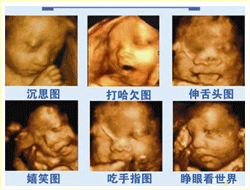

二:引進國際最高水平四維彩超,最低只需1820元。

省內唯一一臺美國GE-v730超高清四維彩超于2011年入駐省級重點婦產科中心——廬江康平產科醫院。現在每日預約四維彩超的女性增加到近百人,為了推動孕產一條路服務質量,414醫院針對建卡女性推出了網絡預約四維彩超最低只需1820元的優惠,由于檢查人員過多,女性需提前預約,不要錯過檢查最佳時間。